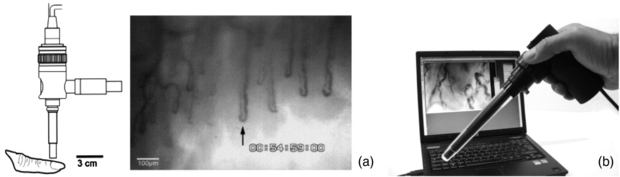

2.4. Nailfold capillaroscopy

Capillaries play a critical role in cardiovascular function as the point of exchange of nutrients and waste products between the tissues and circulation (Shore 2000). Understanding their structure and physiology in health and disease is therefore very important.

2.4.1. Background

Capillaroscopy is a non-invasive imaging technique that is used for in vivo assessment of the microcirculation (Bollinger and Fagrell 1990). It is a microscope technique that allows the morphology of capillary loops to be studied, typically with a 'wide field view' covering a width of a few tens of loops (a few millimetres). It is often applied to the nailfold area of the fingers (NFC) but depending on microscope design could be used to study other areas of the body, including the lips, tongue and mouth (Awan et al 2010, Scardina and Messina 2012, Scardina et al 2013). It is conceptually a simple technique but nevertheless it can provide valuable diagnostic information in the clinical microvascular setting. The nailfolds at the toes can also be studied, however it has been shown this does not provide equivalent diagnostic information to the finger site in patients with either connective tissue disease or vascular disease (Jung and Trautinger 2013).

A principal and validated clinical role is in the differential diagnosis of specific connective tissue diseases, for example SSc (Maricq and LeRoy 1973, Herrick 2008, Cutolo 2010). Other connective tissue diseases of the scleroderma spectrum, such as dermatomyositis, can also be assessed. As well as providing morphological information on capillary structure in health and disease, capillaroscopy can be used to obtain quantitative data such as red blood cell velocities at rest and in response to a stimulus, and also leakage fluorescence studies.

NFC can be performed with various optical instruments, from a standard clinical dermatoscope to a dedicated capillaroscopy system having tailored tissue lighting, a micro-positioner for accurate focusing and image capture and analysis functions. There are commercially-available monochrome and colour systems, some are portable skin contact devices and others non-contact, benchtop microscope configurations. A drop of immersion oil is added to the nailfold to aid visibility of the capillary loops. A cold illumination source is used, e.g. a high intensity LED. In a monochrome system this is often green or blue to give maximal contrast of the red blood cells. A white light source is employed for colour imaging systems. An NFC system needs the correct magnification lens to enable wide field or narrow field views, with these typically quoted as system magnification rather than true optical magnification e.g. x100 for skin width at approximately 3 mm displayed on a standard computer screen or monitor. Close-up lenses are typically x300. Once captured, images can be post-processed to enhance quality, quantitatively analysed to calculate loop size and density, printed in a patient report and archived (figure 13).

Figure 13. (a) Example capillary images from the nailfold region of the finger. (b) KK Technology Capiscope HVCS Handheld Video Capillaroscopy system. The NFC probe has an integral light source and allows images to be collected from the nailfold area, and also sublingually. (Courtesy of KK Technology.)

Download figure:

Standard image High-resolution imageNFC not only can help visualize the surface microvessels by microscopy, it can also be employed in combination with sophisticated methods in order to measure red blood cell velocity (figure 14), capillary pressure (i.e. cannulated capillaries using micropipettes and micropressure devices) (Morris et al 1996, Shore 2000) and transcapillary diffusion of a fluorescent tracer (sodium fluorescein injected intravenously—passage through vessels evaluated with a fluorescence microscope), thus allowing comprehensive physiological and pharmacological studies in humans (Bollinger and Fagrell 1990).

Figure 14. Skin capillaries from anterior aspect of wrist with KK Technology Capillary CAM1 anemometer system velocity recording at a single loop apex. Note the pulsatile component which is superimposed on low frequency vasomotor activity, www.kktechnology.com/cam1.html. (Courtesy of KK Technology.)

Download figure: